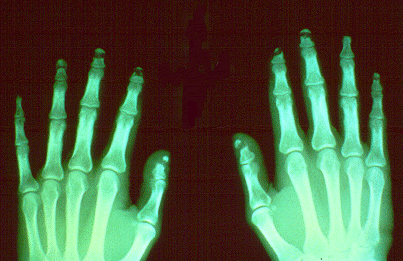

SLIDE 87 - Acroosteolysis, x-rays

Early changes of acroosteolysis can be detected by x-ray. In this radiograph there is dissolution and fragmentation of the bone in several of the terminal phalanges.